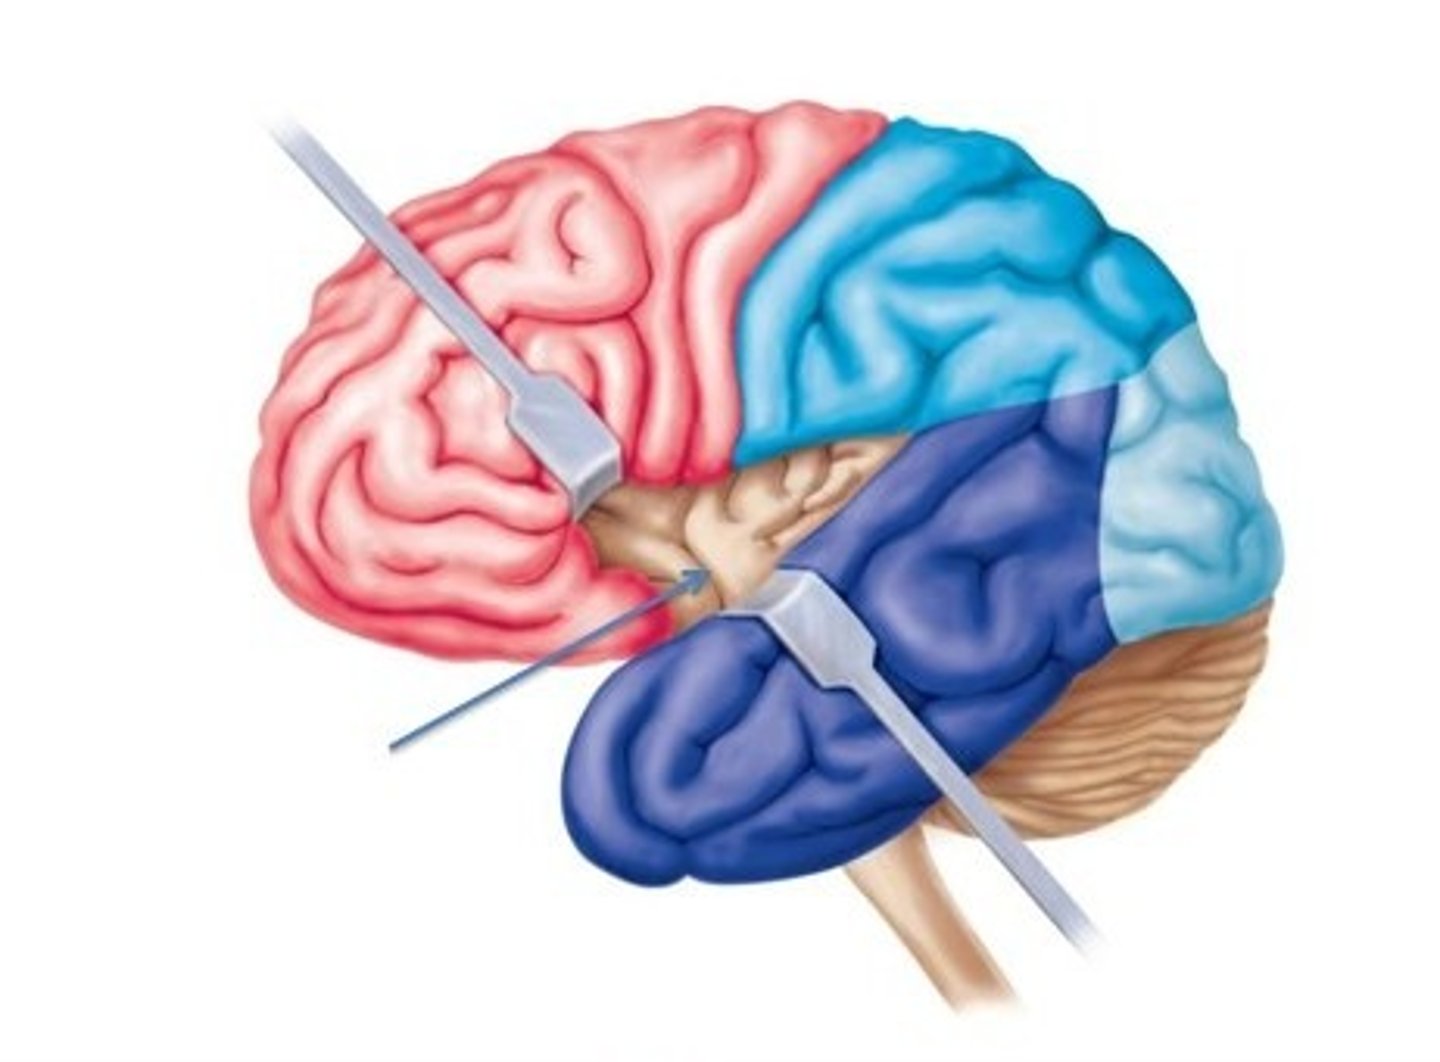

central sulcus

separates frontal and parietal lobes

lateral sulcus

Separates temporal lobe from parietal and frontal lobes